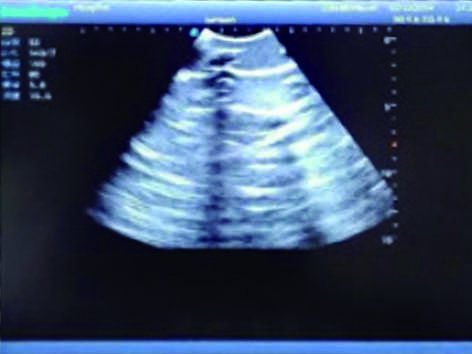

2)  Made of high molecular polymer ultrasound material, close to the real skin. It can conduct ultrasound-guided puncture exercises with various clinical models of real ultrasound machines.

3)  Showing clear and real images of the tissues and organs (including muscle and connective tissue, air-containing lung tissue, pleural structure)